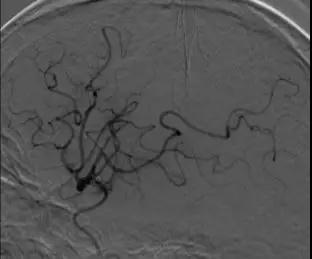

使用4-20 Solitaire 支架进行M2远端分支取栓。 取栓后DSA提示三支病变血管均完全开通。

3. 颈内动脉C1段支架植入。

颈内动脉DSA提示颈内动脉狭窄,远端血流较差。 颈内动脉置入9mm-40mm Protege支架,收回保护伞后DSA提示血管再通良好,给予替罗非班7ml/h。 术后即刻查体NIHSS评分8分,给予替罗非班10ml/h泵入,持续24h。 术后第2天复查灌注成像提示双侧半球基本对称,CTA提示右侧颈内动脉以及大脑中动脉通畅。